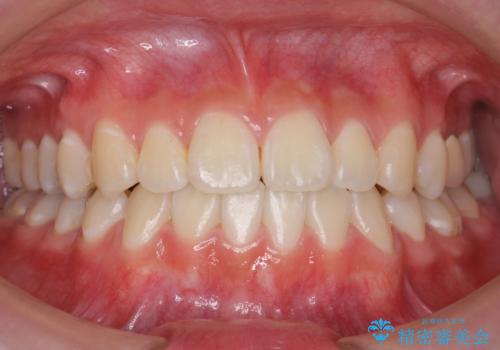

受け口 親知らずを取り込む矯正治療

- 高校生で来院。受け口が主訴でした。

下の小臼歯を抜歯しましたが、その代わり下の親知らずを残して咬ませたので、歯の数は変わっていません。

左上奥歯は、矯正後セラミックインレー修復を行なっています。

親知らずが歯ぐきに埋まっていると不潔になり、炎症を繰り返すため残しておくことが難しい場合が多いです。

今回は左下の小臼歯を1本抜歯してるのと、手術を行なって親知らずを顎に収めることができました。